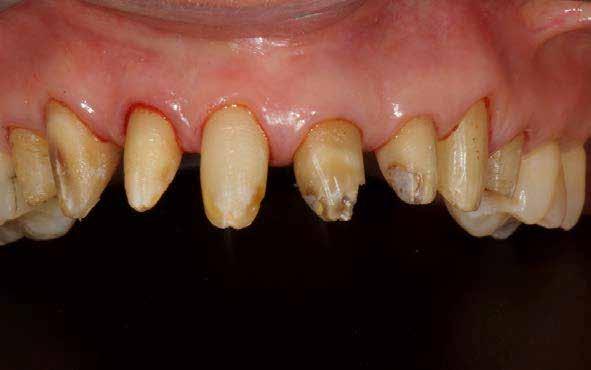

1. ábra: A beteg esztétikai problémájára kért megoldást a régi restaurációk természetellenes megjelenése, továbbá a múltban lezajlott periodontitis következtében kialakult fekete háromszögek miatt. A szövetek visszahúzódása következtében a fogpótlás széle jól láthatóvá vált, a papilla csúcsok elvesztése és a koronák közötti számos fekete térrel együtt, komplex terápiás ellátást igényelt.

2. ábra: A parodontális problémák nem sebészeti kezelési terve a következőkből állt: fogkő-eltávolítás és gyökérsimítás, a korábbi rögzített fogpótlás cseréje, a marginális szövetek helyreállítása, és egy új, esztétikailag kedvezőbb gingivális szerkezet helyreállításának megkönnyítése.